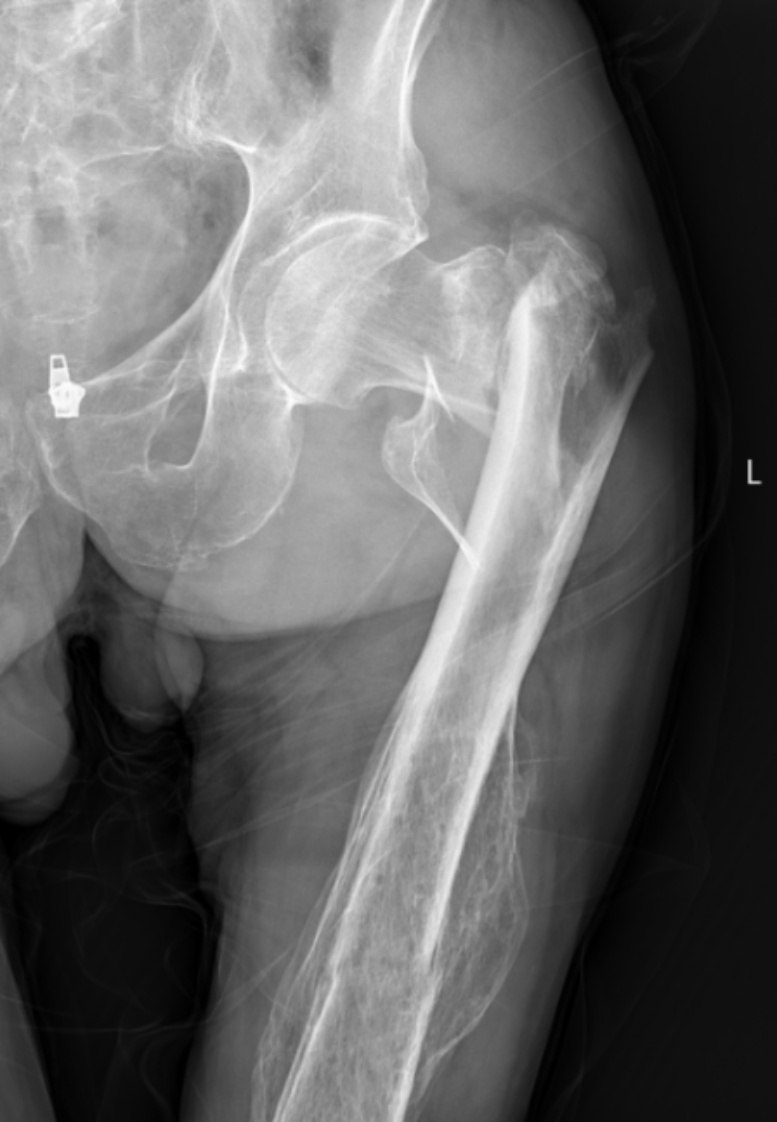

典型病例影像学表现见图1~10。图1为86岁女性右侧股骨转子间骨折(Evans Ⅲ型)患者,术前X线示骨折断端部分错位,术后X线示骨折位置可以及假体位置良好;图2显示了一名81岁男性患者,诊断为左侧股骨转子间骨折,类型为Evans V型,合并股骨干陈旧性骨折。患者接受了生物型加长柄半髋关节置换手术,并进行了股骨近端的钢丝捆扎内固定。术后X线示假体位置良好,股骨近端予钢丝捆扎固定;图3为87岁女性左侧股骨转子间骨折(Evans V型)患者,术后X线示假体位置良好,股骨大小转子骨折位置可,钢丝捆扎固定在位有效;图4为75岁女性左侧股骨转子间骨折(Evans V型)患者,术前X线示左侧股骨转子间骨折PFNA术后、骨折未愈合、内固定断裂。术后假体匹配良好,股骨近端钢丝内固定稳定可靠;图5为75岁男性左侧股骨转子间骨折(Evans IV型)患者,术后股骨大转子出现轻度位移,假体位置正常。图6为87岁男性左侧股骨转子间骨折(Evans V型)患者,给予DAA入路加长柄半髋关节置换,术前X线片,清晰地显示出左侧股骨转子间的骨折情况,术后X线影像,显示股骨的大小转子骨折位置良好,钢丝内固定装置在位稳定,假体位置良好;图7为77岁女性右侧股骨转子间骨折(Evans V型)患者,术前X线片显示右侧股骨转子间存在骨折且股骨大小转子均有累及和移位,术后X线片显示股骨小转子轻度移位,内固定装置位置稳定,假体位置良好;图8为70岁男性左侧股骨转子间骨折(Evans III型)患者,术前的X线片,清晰地显示了左侧股骨转子间的骨折情况,股骨近端髓腔钙化灶,术后假体位置满意;图9为77岁女性右侧股骨转子间骨折(Evans V型)患者,术前X线片,显示右侧股骨转子间及转子下部位骨折情况。术后假体匹配良好;图10为71岁男性右侧股骨颈骨折(Evans IV型)患者,术前X线片,显示右股骨转子间骨折的情况;术后X线表明股骨的大转子和小转子骨折位置保持良好,内固定装置稳固,术后假体位置正常。

(a) (b)

Figure 4. A 75-year-old female patient with left intertrochanteric fracture of the femur (Evans V type). (a) Before surgery; (b) After surgery

4. 75岁女性左侧股骨转子间骨折(Evans V型)患者。(a) 术前;(b) 术后